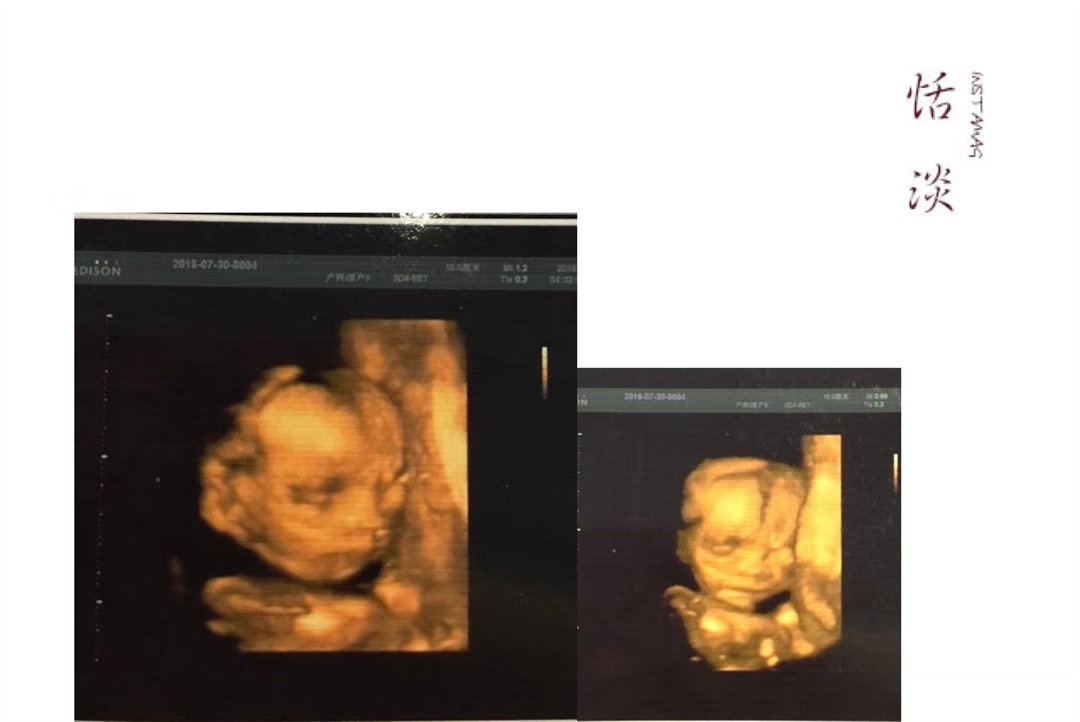

孕35周+4天